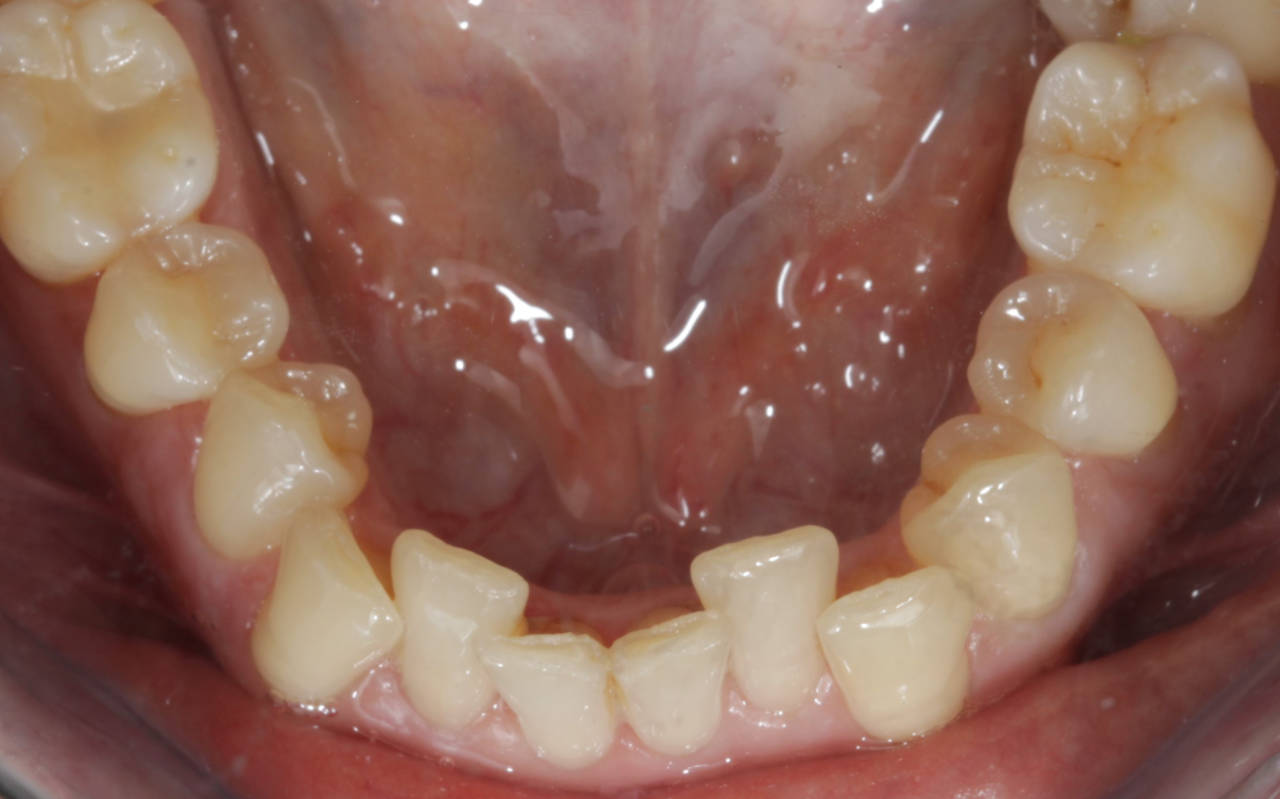

A harmonização do sorriso fez toda a diferença nes